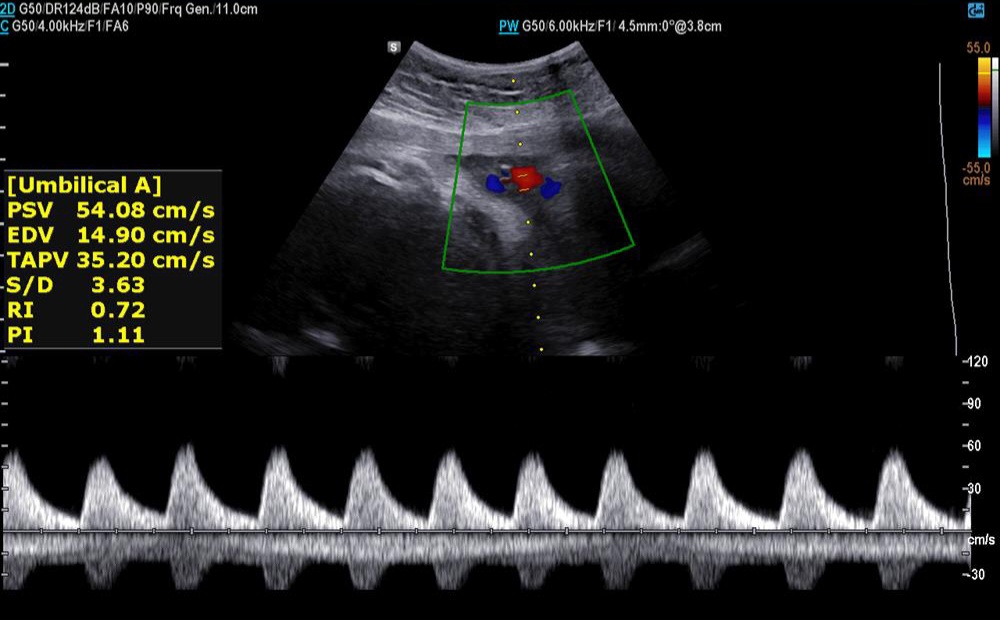

✅️✅️✅️تفسیر سونو داپلر۳۶ هفته🙏🏻

خداروشکر شواهد رشدی بهتر شده و در سونوگرافی شواهدی به نفع محدودیت رشد داخل رحمی و همچنین کمبود اکسیژن جنین وجود ندارد ولی مقداری مقاومت شریانی دارید به پزشکتان حتما مراجعه کنید تا درمورد زایمان و یا شروع انوکساپارین تصمیم گیری شود

جانم pi 2.4 ولی تحت نظر باشید مشکلی ندارد